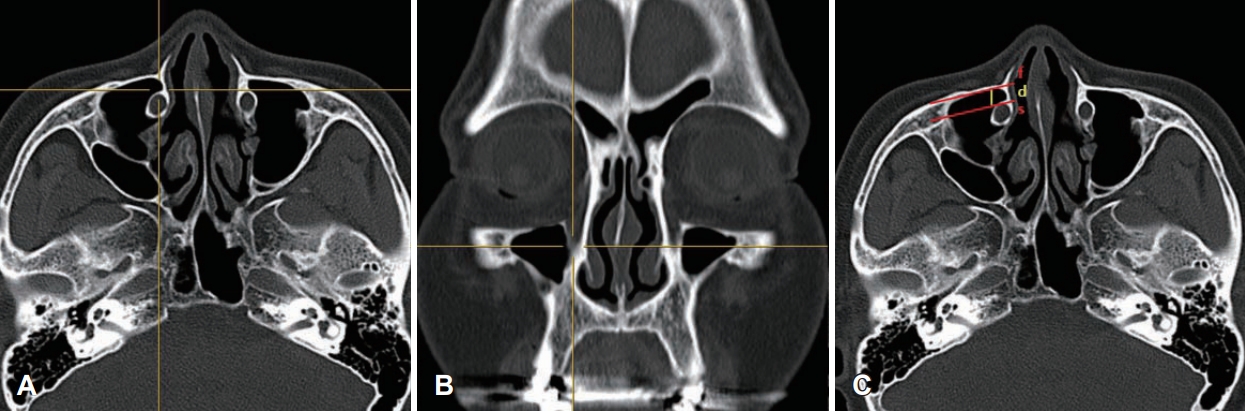

PLRWD 측정은 Simmen 등[6]의 방법대로 부비동 단층촬영의 관상면 영상에서 하비갑개의 앞부분이 상악골의 전두골돌기(frontal process)로의 부착(insertion) 부분을 확인한 후, 축상면 영상에서 그에 해당되는 부분에 3차원 커서를 적용하였다(Fig. 1). 상악동 전벽의 후부를 통해 접선(first line, f)과 누관의 전면과의 평행선(second line, s)을 만든 후 f와 s 사이의 거리(distance, d)를 측정하였다(Fig. 1). 거리가 3 mm 미만은 PLA 타입 I, 3 mm 이상-7 mm 미만까지는 타입 II, 7 mm 이상은 타입 III로 구분하였다.

NotesAuthor contributions Conceptualization: Hyung-Bon Koo, Jae-Hoon Lee. Data curation: Hyung-Bon Koo, Sang-Jun Son. Formal analysis: Hyung-Bon Koo, Sang-Jun Son. Methodology: Hyung-Bon Koo, Jae-Hoon Lee. Supervision: Jae-Hoon Lee. Writing—original draft: Hyung-Bon Koo, Jae-Hoon Lee. Writing—review & editing: Jae-Hoon Lee. Fig. 1.A measurement of prelacrimal recess window distance. A and B: Axial (A) and coronal (B) sinus CT images show the anterior insertion of the inferior turbinate into the frontal process of the maxilla using a three-dimensional cursor. C: An axial sinus CT image shows measurement of a distance (d) between a tangential line (f) through the posterior surface of the anterior wall of the maxillary sinus and a parallel line (s) through the anterior wall of the lacrimal duct. Fig. 2.Internal angle of pyriform notch indicates an angle between a tangential line (f) through the posterior surface of the anterior wall of the maxillary sinus and a line (t) that passes through the frontal process of the maxilla and the inner side of the lacrimal duct. Table 1.Baseline demographics of the study group